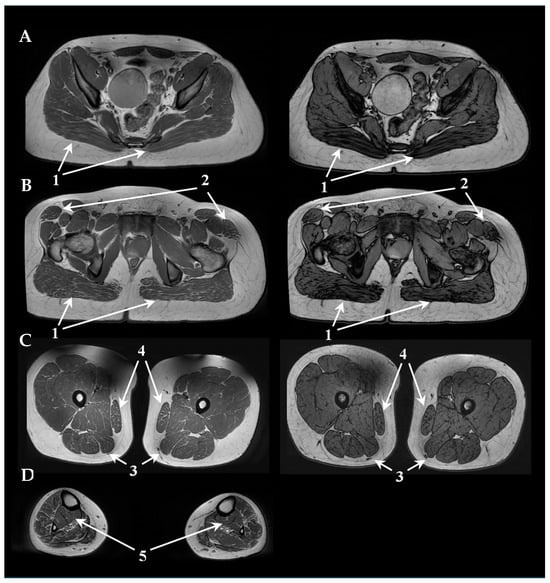

3.2. Neurophysiology and Neuroimaging